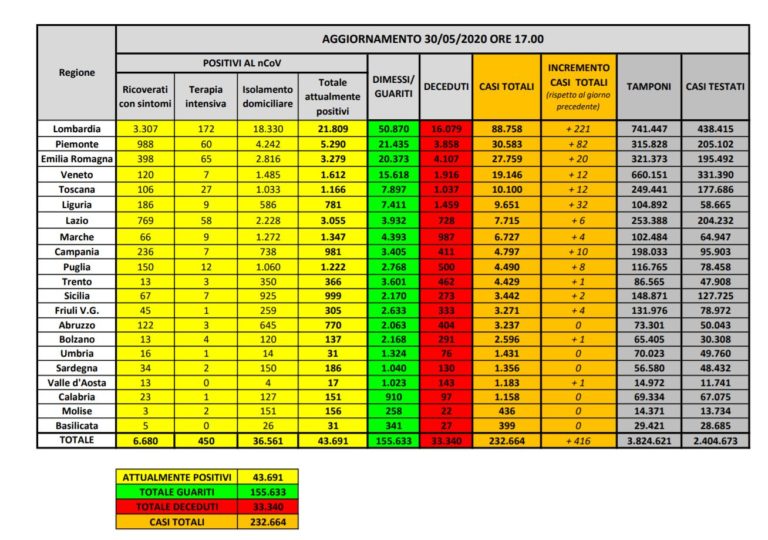

ROMA (ITALPRESS) – Il totale delle persone che hanno contratto il virus finora è di 232.664, con un incremento rispetto a ieri di 416 nuovi casi. Lo riferisce la Protezione Civile nel suo bollettino quotidiano. Il numero totale di attualmente positivi è di 43.691, con una decrescita di 2.484 assistiti rispetto a ieri. Tra gli attualmente positivi, 450 sono in cura presso le terapie intensive, con una decrescita di 25 pazienti rispetto a ieri.6.680 persone sono ricoverate con sintomi, con un decremento di 414 pazienti rispetto a ieri.

36.561 persone, pari all’84% degli attualmente positivi, sono in isolamento senza sintomi o con sintomi lievi.

Rispetto a ieri i deceduti sono 111 e portano il totale a 33.340. Il numero complessivo dei dimessi e guariti sale invece a 155.633, con un incremento di 2.789 persone rispetto a ieri.

Nel dettaglio, i casi attualmente positivi sono 21.809 in Lombardia, 5.290 in Piemonte, 3.279 in Emilia-Romagna, 1.612 in Veneto, 1.166 in Toscana, 781 in Liguria, 3.055 nel Lazio, 1.347 nelle Marche, 981 in Campania, 1.222 in Puglia, 366 nella Provincia autonoma di Trento, 999 in Sicilia, 305 in Friuli Venezia Giulia, 770 in Abruzzo*, 137 nella Provincia autonoma di Bolzano, 31 in Umbria, 186 in Sardegna, 17 in Valle d’Aosta, 151 in Calabria, 156 in Molise e 31 in Basilicata.